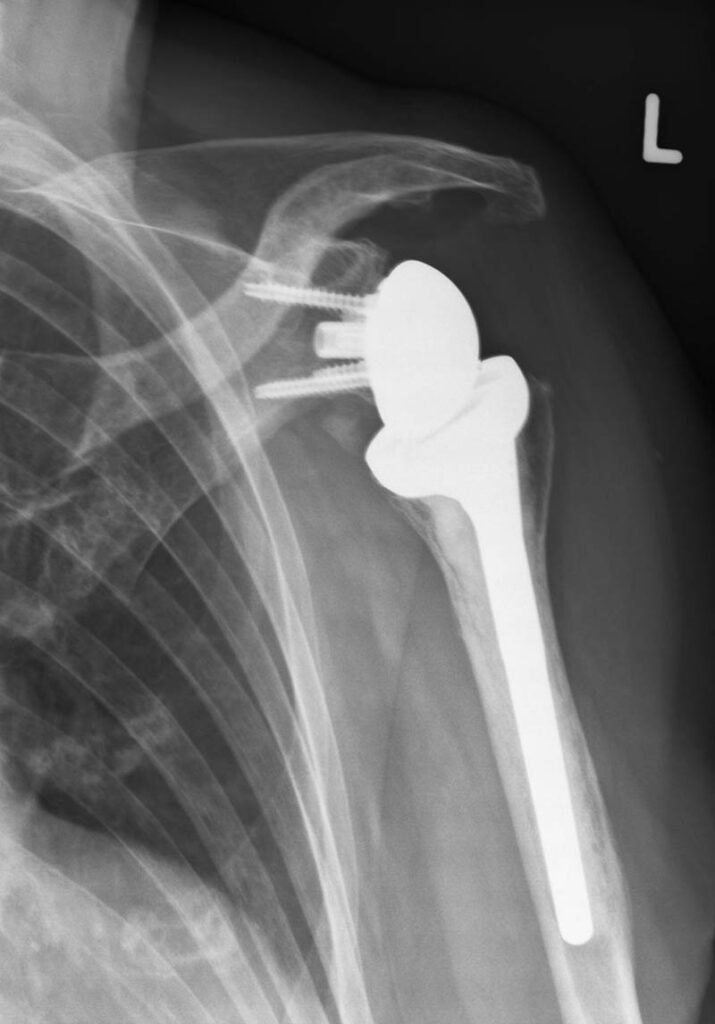

Im Vordergrund der operativen Therapie, die in der Regel erst nach Ausreizen konservativer Maßnahmen in Frage kommt – stellt die Rekonstruktion des Weichteilmantels im Vordergrund. Erst bei fortgeschrittener Arthrose kommt der Gelenkersatz in Frage.

Als moderne Variante des Schultergelenksatzes kommt dem Oberflächenersatz des Schultergelenkes eine immer größere Bedeutung zu: er ermöglicht eine anatomische Rekonstruktion verbunden mit einer sehr guten Funktion.

Röntgen Schulterchirurgie